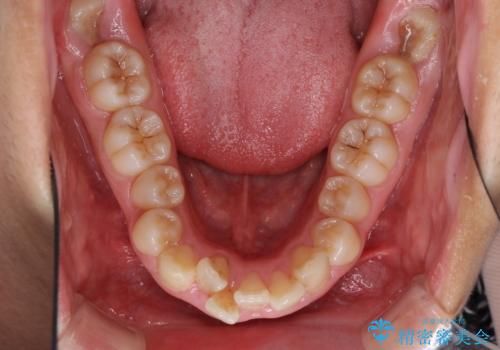

- 上下の出っ歯を気にして来院された患者様です。

口元を積極的に引っ込めるために、上下左右の第一小臼歯を4本抜歯することとしました。

途中で来院されない時期があったため、期間が長引き、更には磨き残しが多かったことで虫歯が多く発現してしまいました。

しっかりと通院するようになってからは順調に治療が進み、横顔の印象が変わるほどスッキリとした口元となりました。